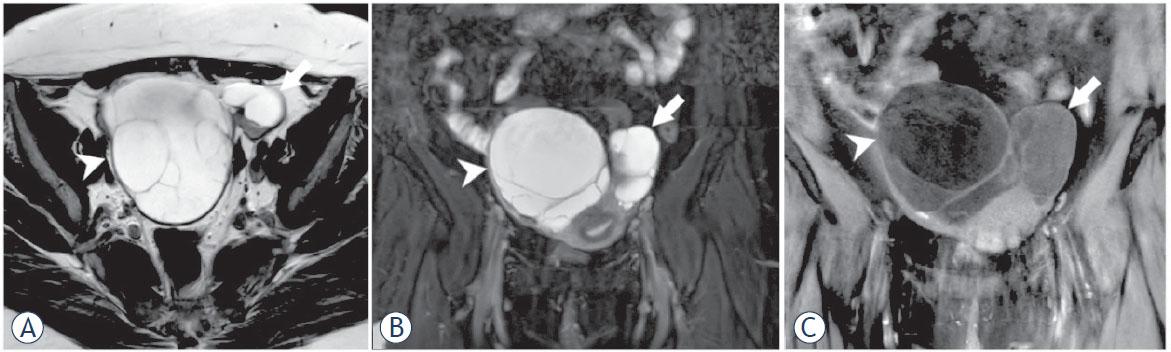

Figure 1